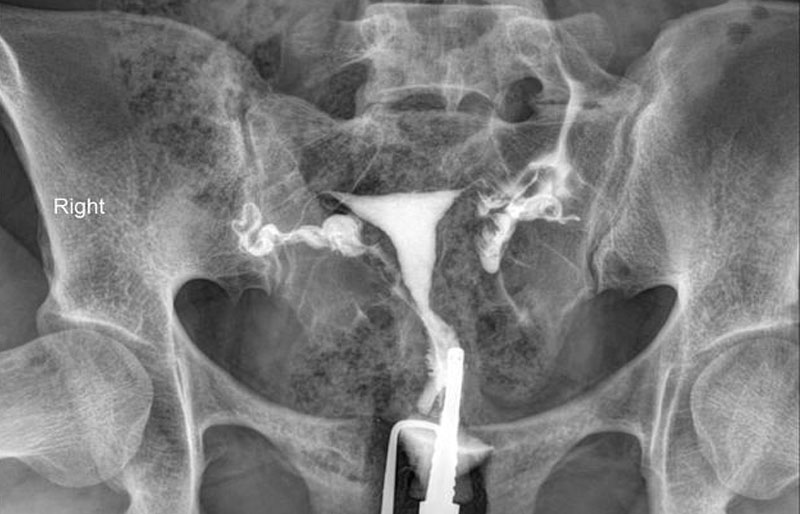

Kỹ thuật chụp tử cung vòi trứng

Chụp tử cung vòi trứng (HSG) là một kỹ thuật chẩn đoán hình ảnh dùng tia X kết hợp với thuốc cản quang để đánh giá hình dạng tử cung và sự thông suốt của vòi trứng. Thủ thuật này giúp phát hiện tắc nghẽn, ứ dịch (hydrosalpinx) hoặc những bất thường ở tử cung như dính, polyp, u xơ, vách ngăn… Từ đó, bác sĩ có thể đánh giá chính xác tình trạng sinh sản và lên kế hoạch điều trị IVF phù hợp.

Thông qua hình ảnh X-quang kết hợp thuốc cản quang, bác sĩ có thể:

- Kiểm tra hình dạng tử cung, phát hiện các bất thường như dính buồng tử cung, vách ngăn tử cung, u xơ tử cung…

- Đánh giá sự thông suốt của vòi trứng, kịp thời phát hiện tình trạng tắc nghẽn hoặc ứ dịch.

Một ống thông mảnh được đưa vào buồng tử cung, sau đó thuốc cản quang được bơm nhẹ nhàng để tạo hình ảnh rõ nét trên X-quang.

Bác sĩ sẽ bơm một lượng nhỏ thuốc cản quang vào tử cung qua cổ tử cung, sau đó chụp X-quang để quan sát dòng chảy của thuốc qua vòi trứng.